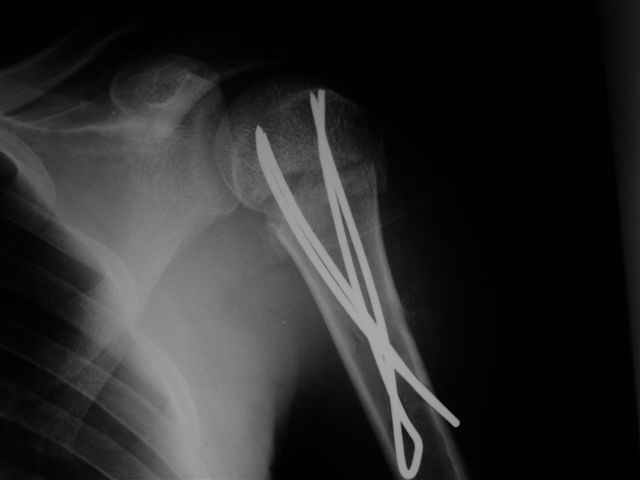

Женя, а как ты водишь спицы, в смысле, как делаешь входное отверстие, и как в него проводишь V-спицу? А то о дна из спиц, та, у которой не дошла до головки одна палочка буквы V, как-то выглядит на рентгенограмме, как будто или через очень большое отверстие введена, или каждая половинка через отдельные отверстия.

В чем ты видишь причину вторичного смещения?

Мне кажется, проблема в том, что не все концы спиц зашли в головку, и зашедшие - недостаточно далеко прошли.

Спицы провожу по передней и задней поверхностям плечевой кости через 4,5 мм отверстия на разных уровнях.

Идеей презентации случая была демонстрация важности постоп Рг - хотя казалось бы все было сделано под флюороскопическим контролем и интраоперационно подозрений на нестабильность не возникло, а такая вот

неожиданность...

Уточни - обе части буквы V вводишь в одно отверстие? А то по снимкам выглядит, что в разные.

V-спица проводится через 4,5 мм отверстие. Видимо, из-за разной длины вторая половина спицы *пролетела* мимо отверстия, что и привело к вторичному смещению костных фрагментов.